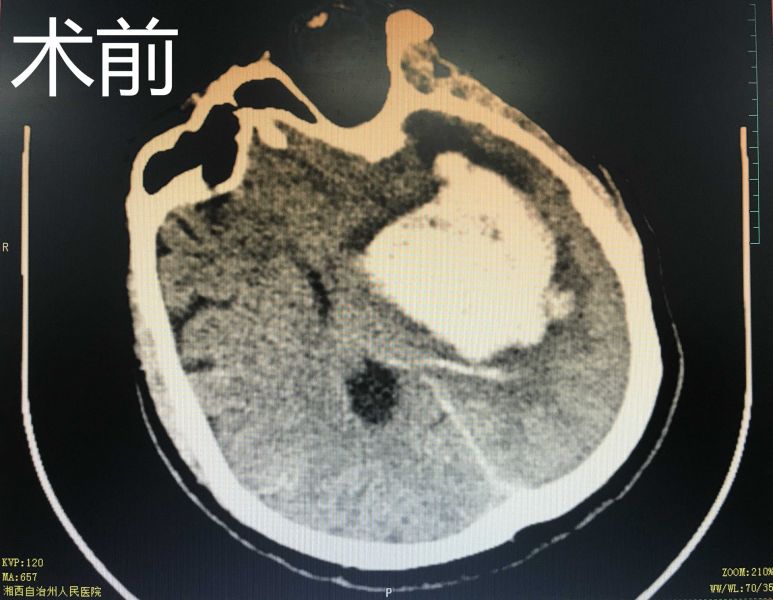

据了解,患者是一名中年男性,突发意识不清2小时入院,头颅CT检查提示:左侧基底节区出血。生死攸关之际,神经外二科主任朱英杰迅速组织术前讨论、分析病情、制定治疗方案。术前在黄纯海副院长的指导下,运用3D Slicer软件中导入CT数据并重建血肿模型,依据血肿模型制定术前计划,规划适合患者的手术路径和手术方式,并利用手机APP辅助增强现实定位技术进行精准的手术入路定位。术中田志副主任与朱英杰主任紧密协作,利用神经内镜辅助通过小骨窗微创完成脑内血肿清除术,手术切口仅4cm。次日病人复查CT颅内血肿清除干净,无残留及再次出血, 病人状态亦明显改善。

术中在神经内镜辅助下清除颅内血肿